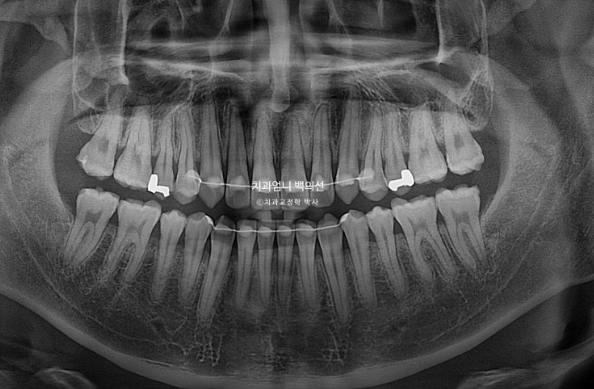

25.03

There is no root resorption, and root parallelism is good.